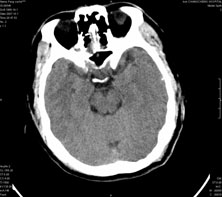

男,41岁,间断抽搐1小时,失神5分钟,bp130/90mmhg。低密度区ct值约16hu。

脑实质见多发散在的钙化点,左顶叶见一囊变灶,多考虑脑囊虫。

脑囊虫,部分囊内见头节。

脑实质见多发散在的钙化点,右颞、顶叶见囊性灶,考虑脑囊虫。

多发的囊泡(多发囊型)+多发的钙化(慢性钙化型)=混合型